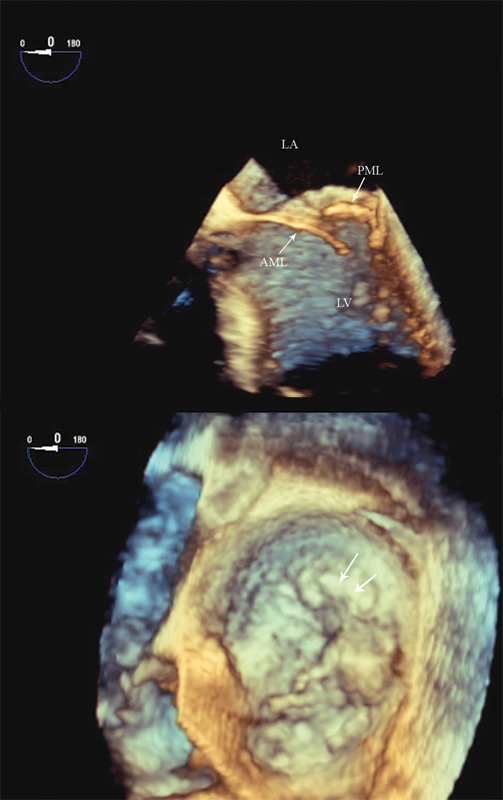

فحوصات تشخيصية لبعض امراض القلب والشرايين التاجية